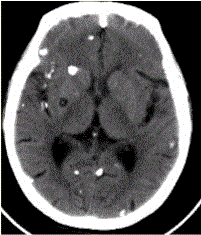

问题 患者男,45岁。头痛、癫痫10余年。查体:无发热,双侧肢体肌力正常。脑电图示双侧额颞叶棘波放电。CT表现如下图。 脑囊虫病的病理演变分为

选项 A.急性期 B.囊胞期 C.胶样囊胞期 D.肉芽肿结节期 E.结节钙化期 F.慢性期

答案 BCDE